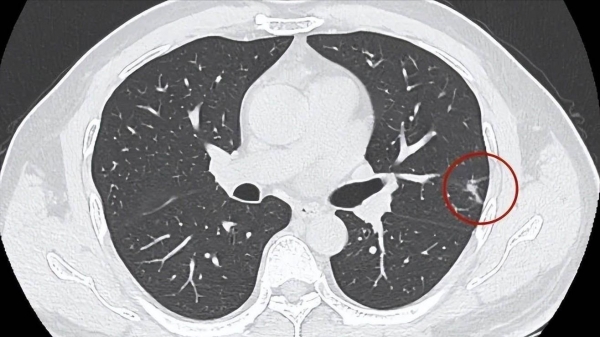

50岁那年,大爷体检查出肺部有结节。他吓坏了,赶紧找了熟人挂上了三甲医院的专家号。

国家卫健委建议:40岁以上人群,应每年进行一次常规体检,高危人群还应进行针对性筛查,例如肠镜、HPV检测、低剂量CT等。